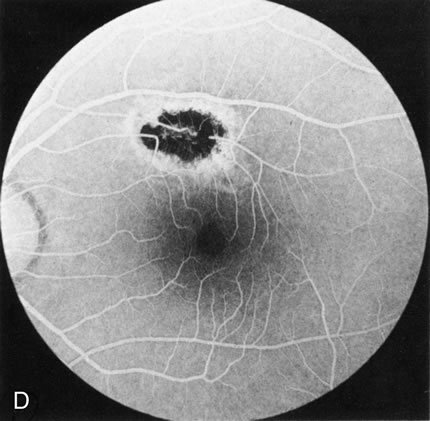

Of more clinical importance is the role of FA in the diagnosis and treatment of cystoid macular edema (CME) (Fig. 1C and D). Stereoscopic FA indicates that the leakage, which may be diffuse or have the typical petaloid stellate appearance of CME, can come from the perifoveal retinal capillaries, from the choroid through the RPE, or from a combination of both sources.4 With the recent suggestion that CME in RP may be successfully treated with acetazolamide,5, 6 FA is thus important to document the diagnosis of CME, establish the origin(s) of leakage, and follow patients during and after therapy.